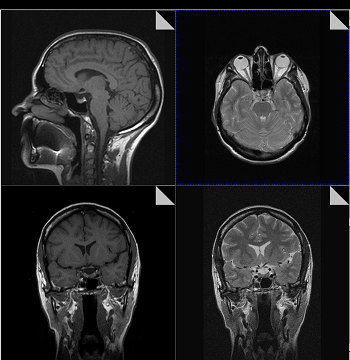

Магнитно-резонансная томография

В основе МРТ лежит явление магнитного резонанса, основанного на переизлучении радиоволн, взаимодействующих с атомами водорода, в избытке содержащимися в организме человека. Эти переизлученные электромагнитные волны улавливаются датчиком МР-томографа, усиливаются и в виде цифровых изображений появляются на экране монитора. Это безвредный и абсолютно безопасный для здоровья человека метод лучевой диагностики, так как в основе получения изображения отсутствует рентгеновское излучение, поэтому МРТ можно проходить неограниченное количество раз, с любым интервалом.

Существенное преимущество МР-томографии перед КТ заключается в том, что она не противопоказана беременным во II и III триместре и совершенно безопасна для детей. В МРТ исследуемая область сканируется в трех проекциях, что позволяет врачу-рентгенологу в полной мере оценить состояние тканей и органов исследуемой области, а высокая контрастность изображения и пространственное разрешение позволяют визуализировать серое и белое вещество головного мозга, оценивать состояние костного мозга и мягких тканей различной локализации. Кроме того, метод МРТ позволяет получать изображения сосудов головного мозга и сосудов шеи без введения контрастного препарата.